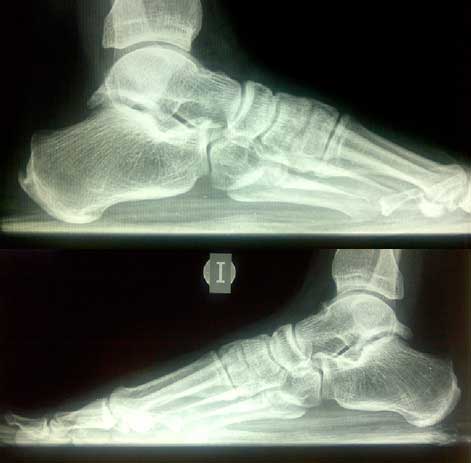

Diagnostico: tendinitis calcica del Aquiles bilateral.

Estudios realizados: Rx/ calcificación del Aquiles y eco confirma lesión.

Tratamientos realizados: AINES , no infiltraciones , rehabilitación con láser y ultrasonido.

Ultimo tratamiento: Se somete al paciente a Ondas de Choque.

Resultados en pie dcho.:

1ª sesión…………………………………………. Dolor de 7-8

2ª sesion…………………………………………. Dolor de 5

3ª sesion…………………………………………. Dolor de 3

4ª sesion…………………………………………. Dolor de 2

5ª sesion…………………………………………. Dolor de 0

Resultados en pie izq.:

1ª sesión…………………………………………. Dolor de 6

2ª sesion…………………………………………. Dolor de 4

3ª sesion…………………………………………. Dolor de 4

5ª sesion…………………………………………. Dolor de 1

6ª sesion…………………………………………. Dolor de 0

Damos el alta a la espera de 1 mes de evolución y una nueva Rx. Y ecografía. derivamos al medico prescriptor que en este caso fue el Dr. Larrainzar.